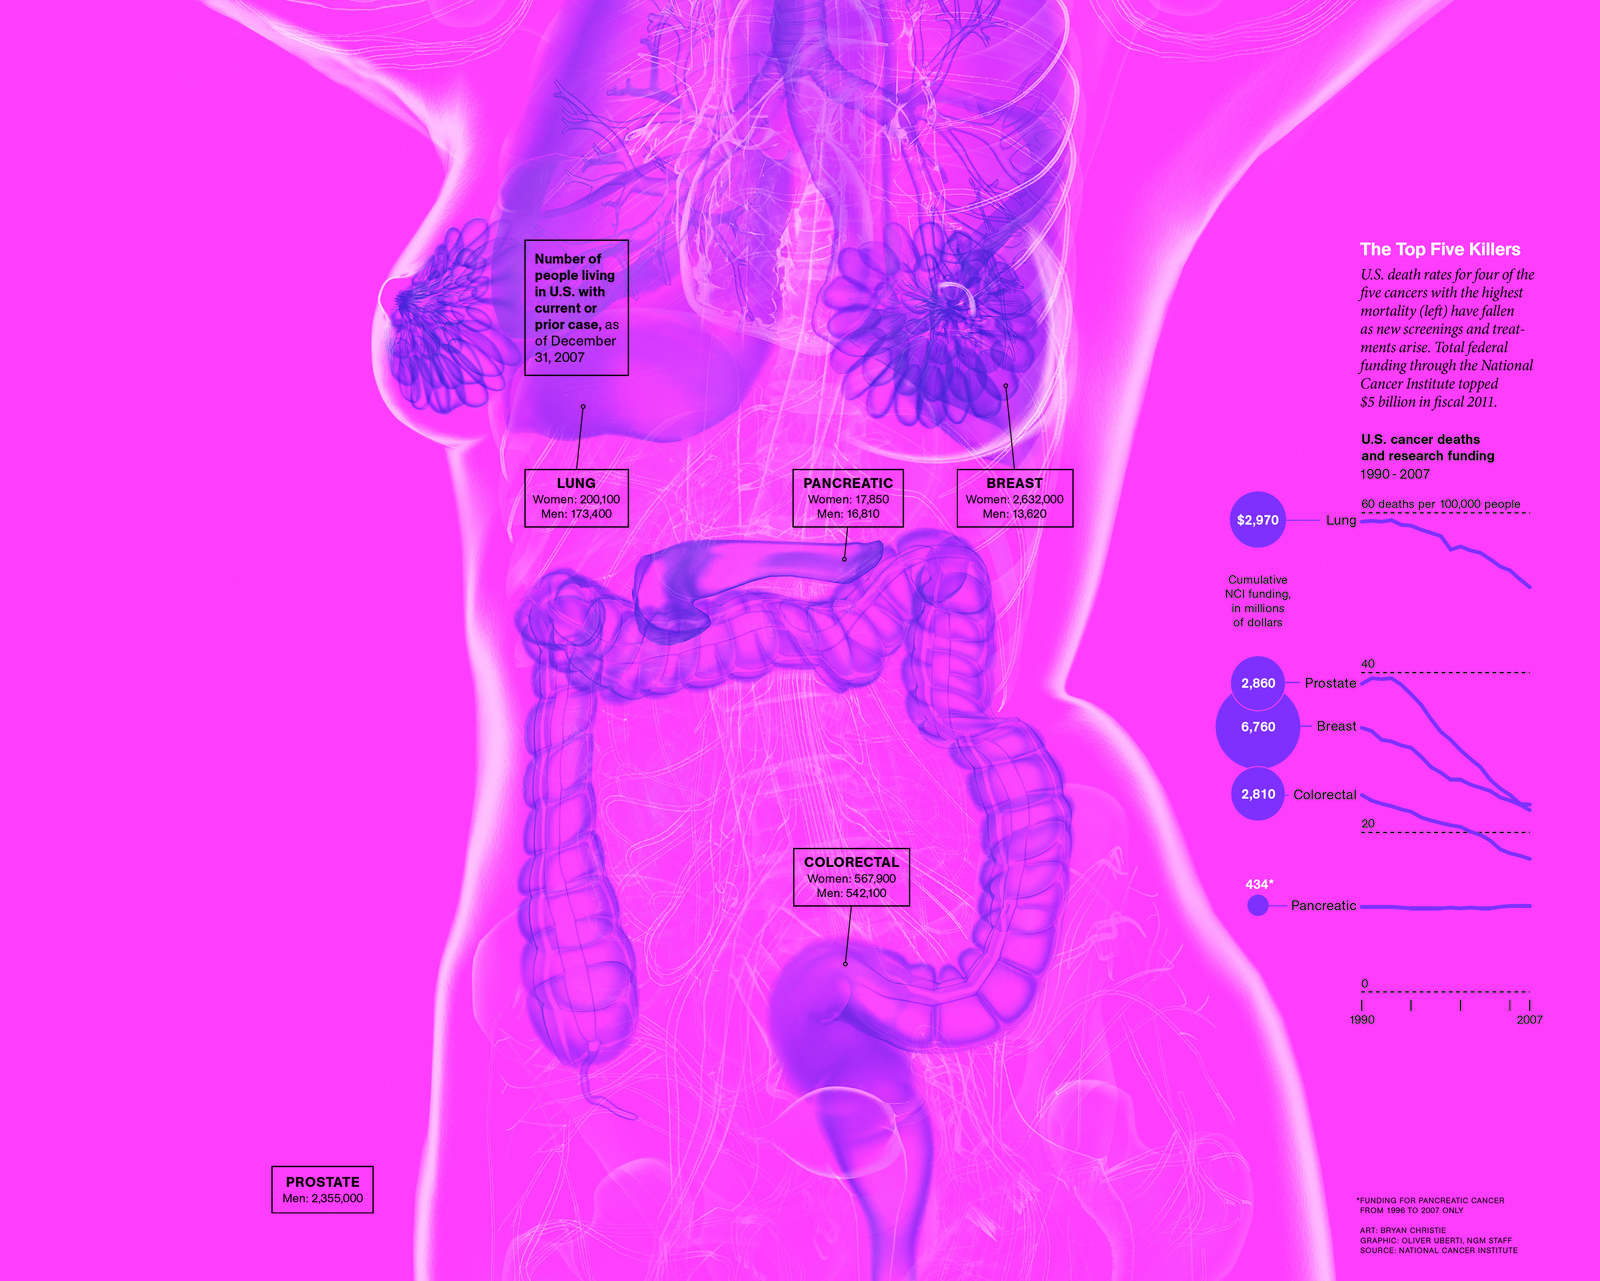

9. The five cancers with the highest mortality rates are breast cancer, prostate cancer, pancreatic cancer, lung cancer, and colorectal cancer: